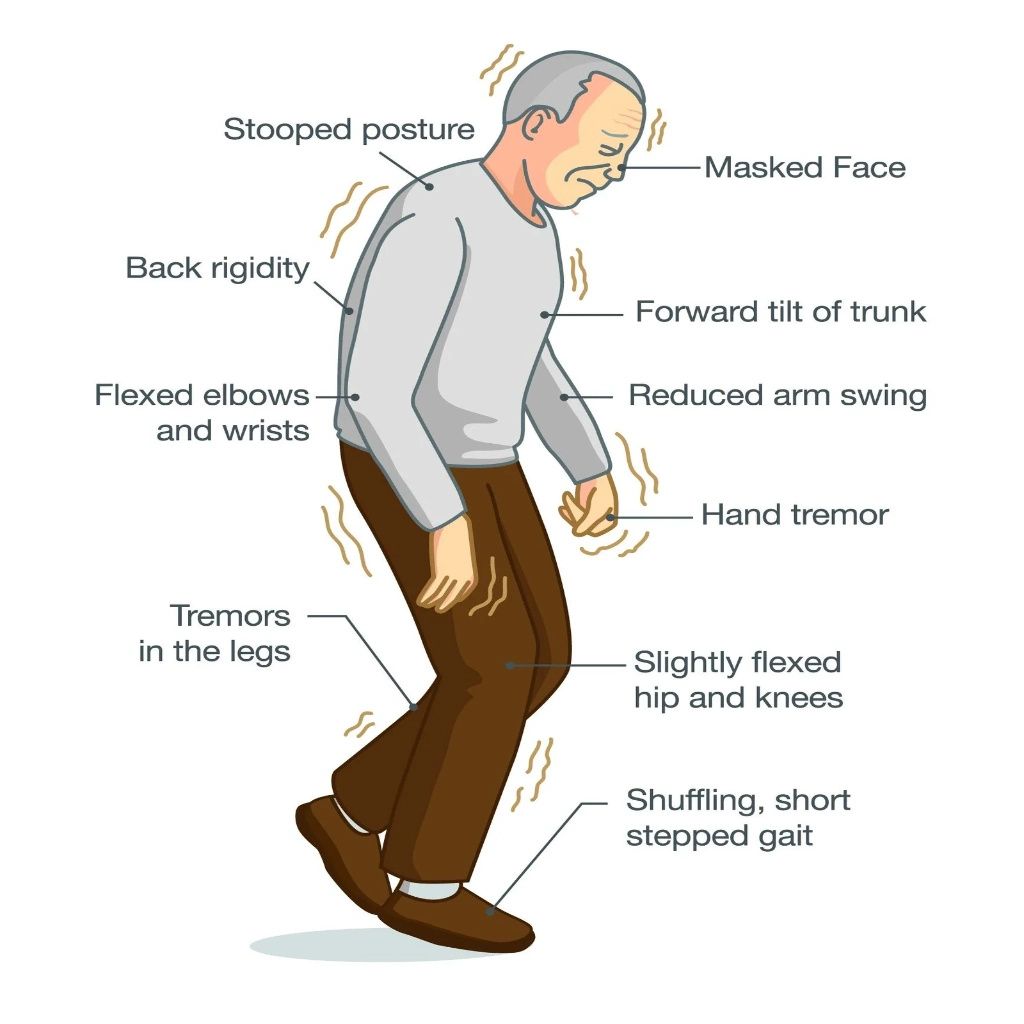

As a specialist in Functional Neuromodulation Surgery, he offers advanced treatments including Deep Brain Stimulation (DBS) for Parkinson’s disease, epilepsy surgery, and procedures for chronic neurological conditions. He is among the first neurosurgeons in Gujarat to develop expertise in this highly specialized field.

Pioneer of Functional Neuromodulation Surgery in Gujarat

Dr Chirag Solanki, the best Neurosurgeon in Gujarat as expertise in treating a wide range of neurological conditions, including brain strokes, aneurysms, brain tumors, Parkinson’s disease, tremors, dystonia, epilepsy, pain, incontinence, psychosurgeries, spine problems and spinal tumors and traumatic brain injuries. We also offer comprehensive care options, from minimally invasive procedures to complex surgical interventions.